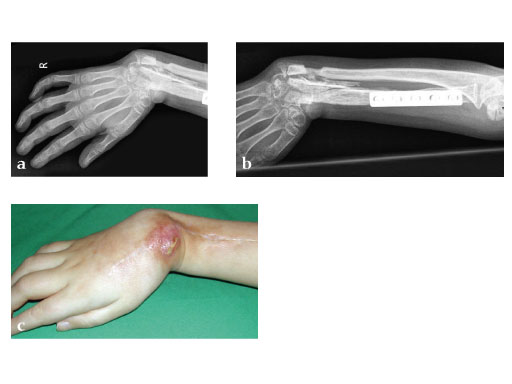

Fig 5ab: Outcome after 2.5 months.

Case provided by Martin Langer, Mnster, DE